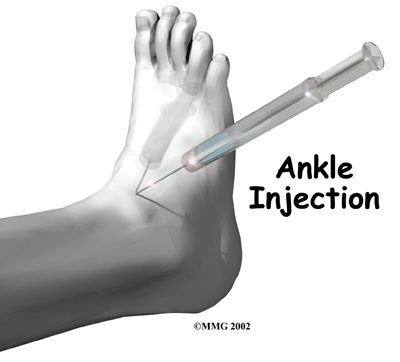

Rehabilitation services, such as those offered at STAR Physical Therapy, play a critical role in the treatment plan for ankle joint arthritis. Treatment usually begins when the ankle first becomes painful. The pain may only occur at first with heavy use and may simply require the use of mild anti-inflammatory medications such as aspirin or ibuprofen. Reducing the activity or changing from occupations that require long periods of standing and walking may be necessary to help control the symptoms.

Braces that reduce the motion in the ankle can also be beneficial in reducing pain. Special braces that transfer some of the body weight to the knee can help protect the ankle. These braces are called patellar tendon bearing braces. They are quite large and bulky and may not be well tolerated by some patients.